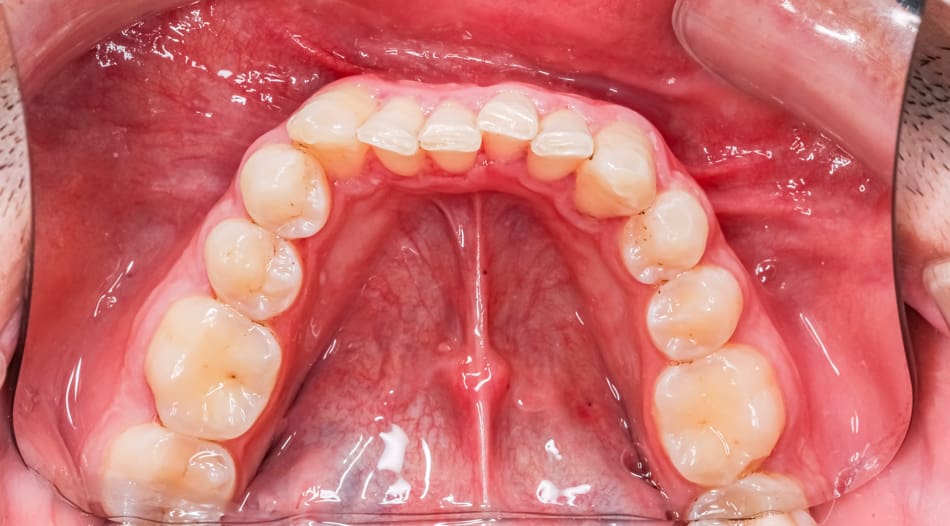

Everyone has a small band of tissue (frenum) that connects the tongue to the floor of the mouth and the lips to the gums. When this tissue is too thick, tight, or short, it restricts movement. A frenectomy is a simple procedure to release this band.